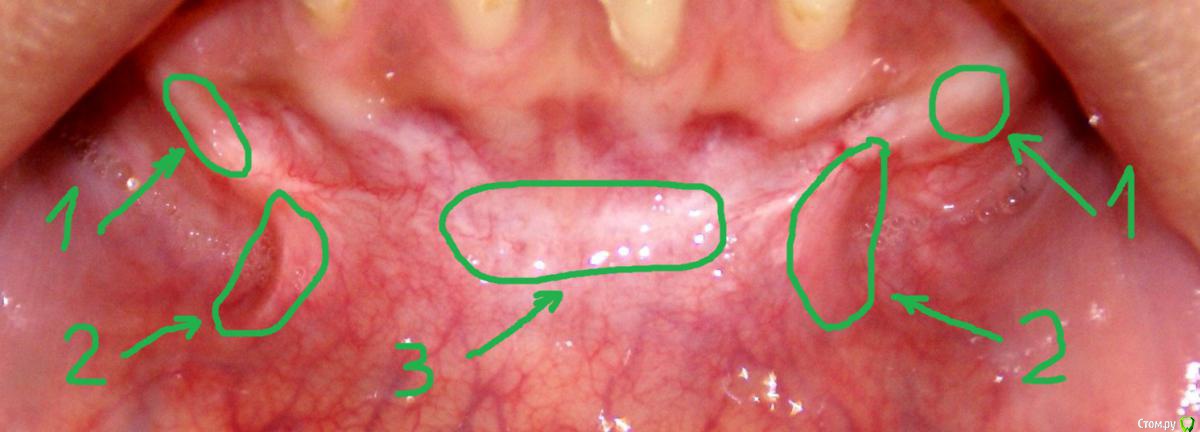

колесников Опубликовано 15 июня, 2017 Поделиться Опубликовано 15 июня, 2017 По уровню прикреплённой десны ситуация выглядит лучше,стабильнее чем до вмешательства. После вмешательств такого рода часто случаются рецидивы и неудачи,у Вас их нет. Но случаются и побочные "осложнения",в частности у Вас образовались тяжи в области клыков,которых раньше не было. Запргнозировать их оборазование зачастую невозможно. Это мягкие ткани,их можно попробовать "растянуть" или размягчить,делая миогимнастику,(надувая пузырь под губой),если это не поможет,дополнительная пластика по устранению этих тяжей. Ссылка на комментарий

Irina_S Опубликовано 16 июня, 2017 Автор Поделиться Опубликовано 16 июня, 2017 у Вас образовались тяжи в области клыков,которых раньше не было. А можно Вас попросить уточнить, что Вы называете тяжами?Под номером 1, под номером 2 или и то и другое вместе? Ещё вот такая хронология: 24 октября была сделана вестибулопластика, 28-го сняли швы, до 13 ноября я касалась кончиком языка "кармана" в глубине линии разреза, отметила это на фото, чтобы было понятно, о чём речь. 14 ноября проводилась обработка зубов с помощью аппарата Вектор и были заложены саморассасывающиеся лечебные повязки на обе челюсти, в том числе и в этот "карман". В этот день увидела, что "карман" визуально склеился из-за заложенной повязки, и я перестала на несколько дней делать упражнения с надуванием губ и касанием кончиком языка.А потом этот "карман" исчез и в итоге получилась поверхность, обозначенная на первой картинке под номером 3. Вопрос: мне не надо было допускать срастания двух поверхностей слизистой, чтобы этот "карман" остался, или его исчезновение и должно было произойти в процессе заживления? (думаю, что это срастание и вызвало ощущение стягивания и уплотнения внутри подбородка в виде инородного тела) Ссылка на комментарий

Irina_S Опубликовано 19 июня, 2017 Автор Поделиться Опубликовано 19 июня, 2017 келоидных рубцов на слизистой не бывает, успокойтесь. Хорошо, пусть будут просто какие-то рубцы. Я хочу понять, фрагменты под номерами 1 и 2 - это части одного длинного тяжа, которые выглядят по-разному, потому что находятся в разных местах, или это вообще разные образования, и тяж - это только номер 2? Ссылка на комментарий